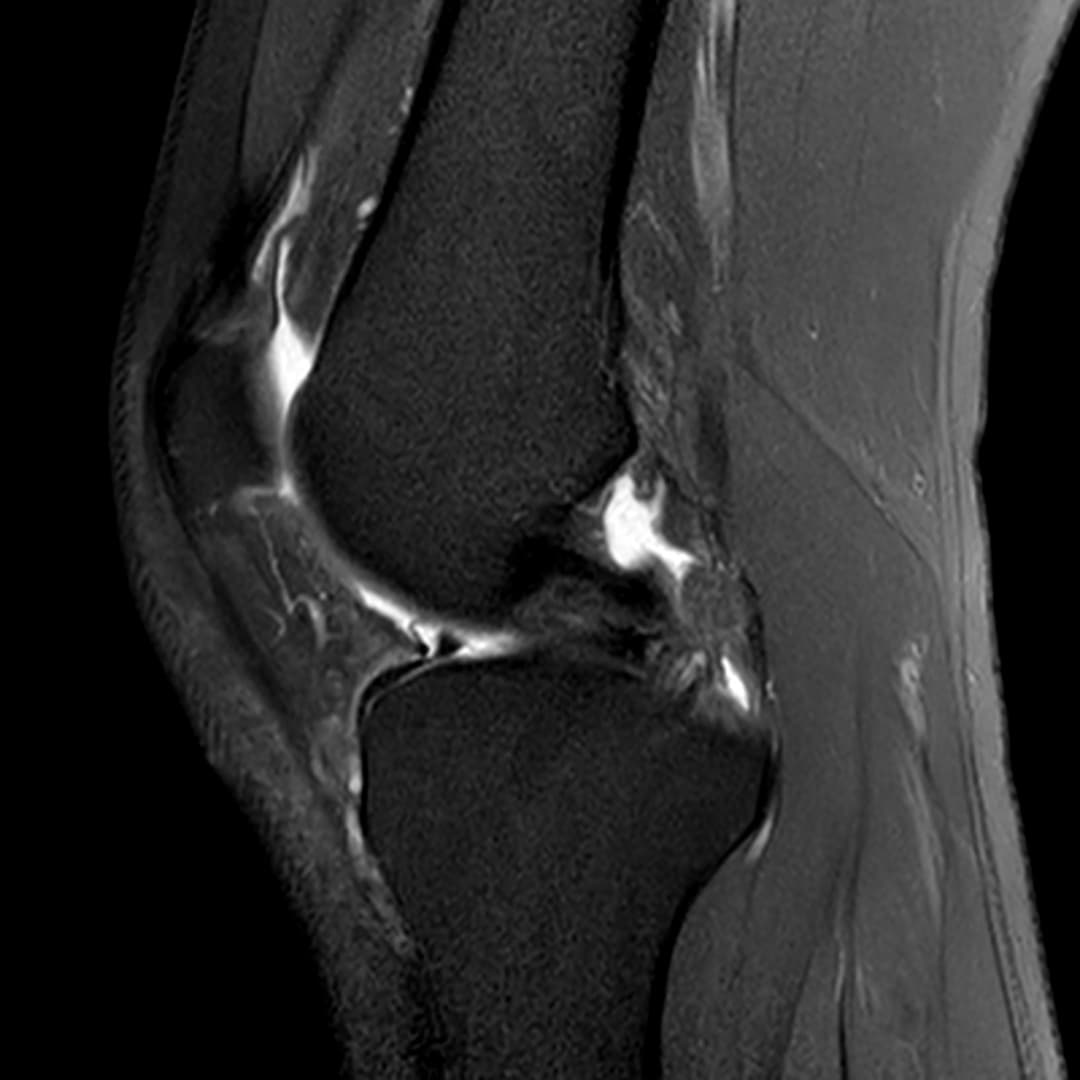

Languette méniscale rattachée à la corne antérieure du ménisque médial avec aspect flottant sur le versant antérieur de l'échancrure.